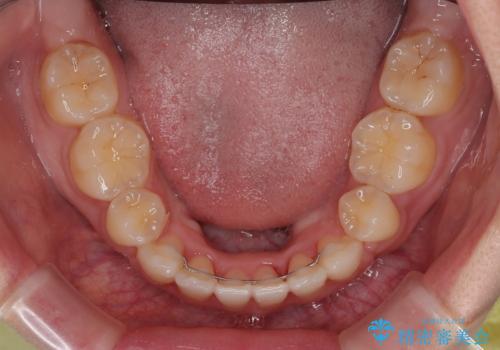

口元の突出感が改善されてことで、下唇に引っかかっていた上顎前歯も気にならなくなりました。